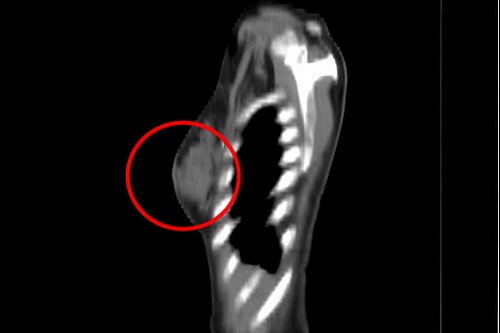

隨著微創手術器械的進展,有些患者可以進行內視鏡輔助整型式乳癌切除手術,從位於胸部側邊靠近腋下約五公分大小的單一傷口,進行腋下淋巴結取樣或清除,並由此進行乳房部分切除手術,將所要切除的乳房組織取出後再進行乳房整型修補。張群明主任分享,經醫師評估腫瘤的大小與位置,合適者可以進行「內視鏡輔助整型式乳癌切除手術」,以自己的乳房做整型修補,術後乳房不會產生凹陷且不會在乳房上留下任何傷口。

▲張群明主任說,「內視鏡輔助整型式乳癌切除手術」,以自己的乳房做整型修補,術後乳房不會產生凹陷且不會在乳房上留下任何傷口。